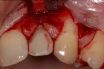

Socket

Any opening or hollow that forms a holder for something, e.g., a tooth. A hollow part in a bone, into which another bone or organ fits. Bony hollow into which a structure fits; the orbits are informally referred to as “eye sockets.” A hollow or depression into which another part fits, such as the cavity…